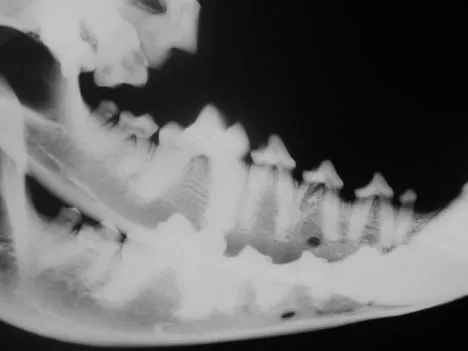

It is less convenient and more technically difficult to obtain high-quality dental images with traditional radiographic techniques. The radiograph machine is usually distant from the dental operatory, making it necessary to move the patient to obtain radiographs. Positioning is more difficult because the tube head is stationary. The need for extraoral film placement increases the difficulty of avoiding overlapping of structures. Dental films placed intraorally can be used with a standard radiographic machine to help with some of these problems; however, the practitioner wishing to incorporate dental radiology into his or her practice is advised to invest in a dedicated dental unit.

Skulls were used for these images. Dental images were obtained with a digital sensor; the traditional radiographs were taken using extraoral technique with a standard radiographic machine.

A lateral radiograph of a dog's skull shows the upper and lower jaw with clearly defined teeth and roots. The image highlights dental structures, including potential abnormalities such as tooth alignment and bone density.

A radiograph displays the lower jaw of a canine, highlighting the alignment and condition of the teeth and jawbone. The image reveals the dental structure, including the roots and crowns of the teeth, providing insights into potential dental issues.